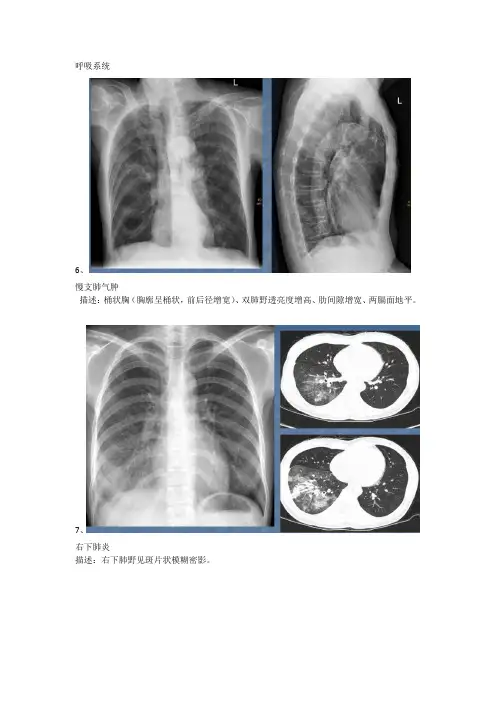

呼吸系统6、慢支肺气肿描述:桶状胸(胸廓呈桶状,前后径增宽)、双肺野透亮度增高、肋间隙增宽、两膈面地平。

7、右下肺炎描述:右下肺野见斑片状模糊密影。